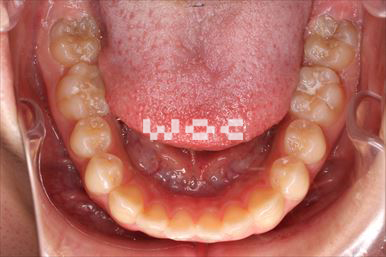

出っ歯上のみ舌側矯正、下はエッジワイズ装置

上は舌側矯正で希望。第一選択は上顎両側第一小臼歯の抜歯だったが、ボーダーラインケースであり改善なければ抜歯することを了承のうえ、非抜歯治療で開始。非抜歯で終了しました。

- 年齢:28歳女性

- 主訴:出っ歯、前歯が曲がっているのが気になる

- 基本矯正料金:103万円

- 治療期間:1年8ヶ月

- 非抜歯